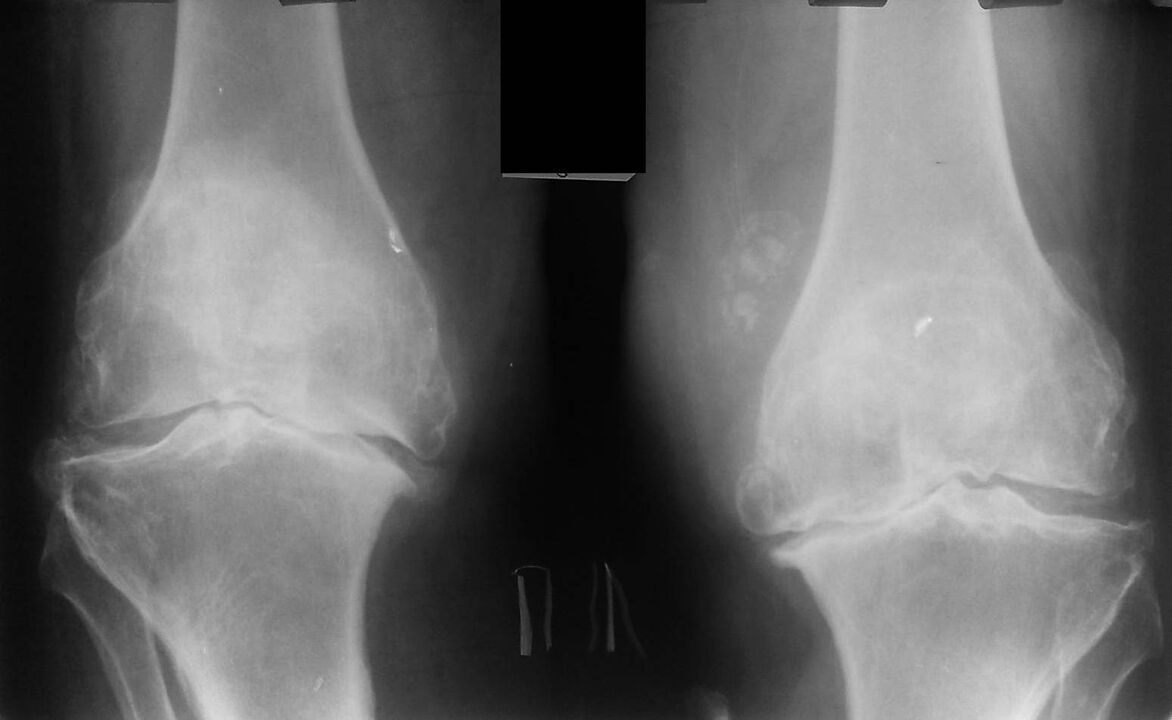

Diese Diagnose wird auf der Grundlage der Beschwerden des Patienten, der Untersuchungsdaten, der Palpation des erkrankten Gelenks und der Röntgenuntersuchung gestellt.

Die Radiographie ist eine Standardforschungsmethode, mit der Sie die Diagnose bestätigen, den Grad pathologischer Veränderungen feststellen, die Dynamik des Prozesses überwachen und andere pathologische Prozesse (z. B. Tumore) in Tibia und Femur ausschließen können. .

Es sollte beachtet werden, dass primäre Veränderungen in den Strukturen des Kniegelenks auf Röntgenaufnahmen fehlen können. Anschließend werden die Einengung des Gelenkspalts und die Verdichtung des subchondralen Bereichs bestimmt. Die Gelenkenden des Femurs und insbesondere der Tibia erweitern sich, die Kanten der Kondylen werden spitz.